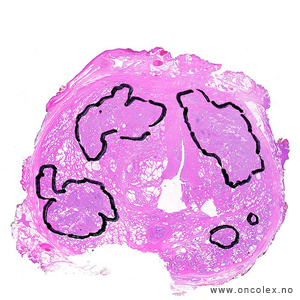

Analyse av vevsprøver

Vevsprøver sendes til histologisk analyse. Analysene kan være avgjørende for hvilken behandling pasienten får. Når patologen undersøker vevsprøvene i mikroskop blir det angitt hvor det er påvist kreft, hvor mange millimeter karsinom det er i hver vevsprøve i forhold til den totale mengde av vevsprøver. Det angis også om det er kribriform vekst, perinevral infiltrasjon og infiltrasjon i fettvev eller sædblærer (vesicula seminalis), hvis dette er kommet med i vevsprøvene. Vevsprøven typebestemmes og graderes (Gleason og/eller ISUP).

95 % av kreftsvulstene i prostata er adenokarsinomer som utgår fra kjertelendestykkene og gangene i prostata. De vokser multifokalt i prostata og gir ofte ingen synlige tumorknuter i mikroskop. Vel 75% av tilfellene oppstår i bakre del av prostata.

Bildeeksempler av vevsprøver

I operasjonspreparater etter kirurgisk fjerning av prostata, der svulstvevet som regel har flere utgangspunkter, angis bare punktet med høyeste Gleasonscore/ISUP og eventuelt tertiær Gleasongrad 4–5.